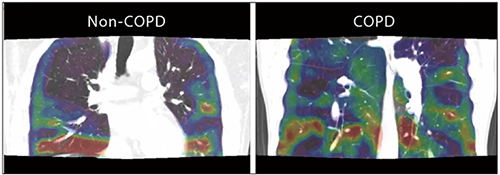

また、さらに進んだPhyZiodynamicsによる呼吸ダイナミックCTの解析として、strain mappingが挙げられる。この解析法は、基準の時相を設定した上で、時相の変化に伴って生じる、肺内の架空の六面体の“歪み度”を全肺にわたって表したもので、単なる移動量や回転量の成分を排した“最大主歪み”を表現するとされる。この解析法は、元は拍動下の心筋の異常運動を可視化するために開発されたものと思われるが、COPD患者の呼吸ダイナミックCTに応用することで、“肺の中の不均一な呼吸運動”を容易に可視化することができる(図4)。今後は、このstrain mappingを用いた、COPDなど各種閉塞性疾患の病態解析にも乗り出していきたいと考えている。

図4 PhyZiodynamicsによるstrain mapping解析

非COPD患者よりもCOPD患者で肺の呼吸性運動の“歪み”が強い。